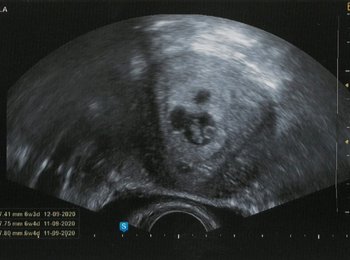

Ahoj Janiiii!!!! Neuvěřitelné se stalo skutečností po dvou letech. Na kurzu v Ostravě s Tebou jsem byla 17. října, po té jsem poctivě cvičila 6x týdně ráno před prací a 26. prosince jsem našla dvě čárky. A dneska na ultrazvuku je nás vidět víc než jsme čekali :-) Děkuji, jsi zlato. :-*